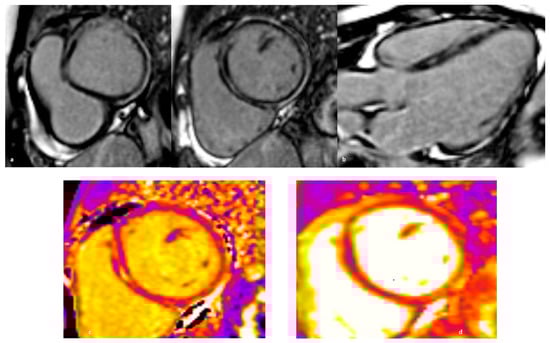

3.2. Clinical Features and Diagnosis

4.2.2. Diagnostics